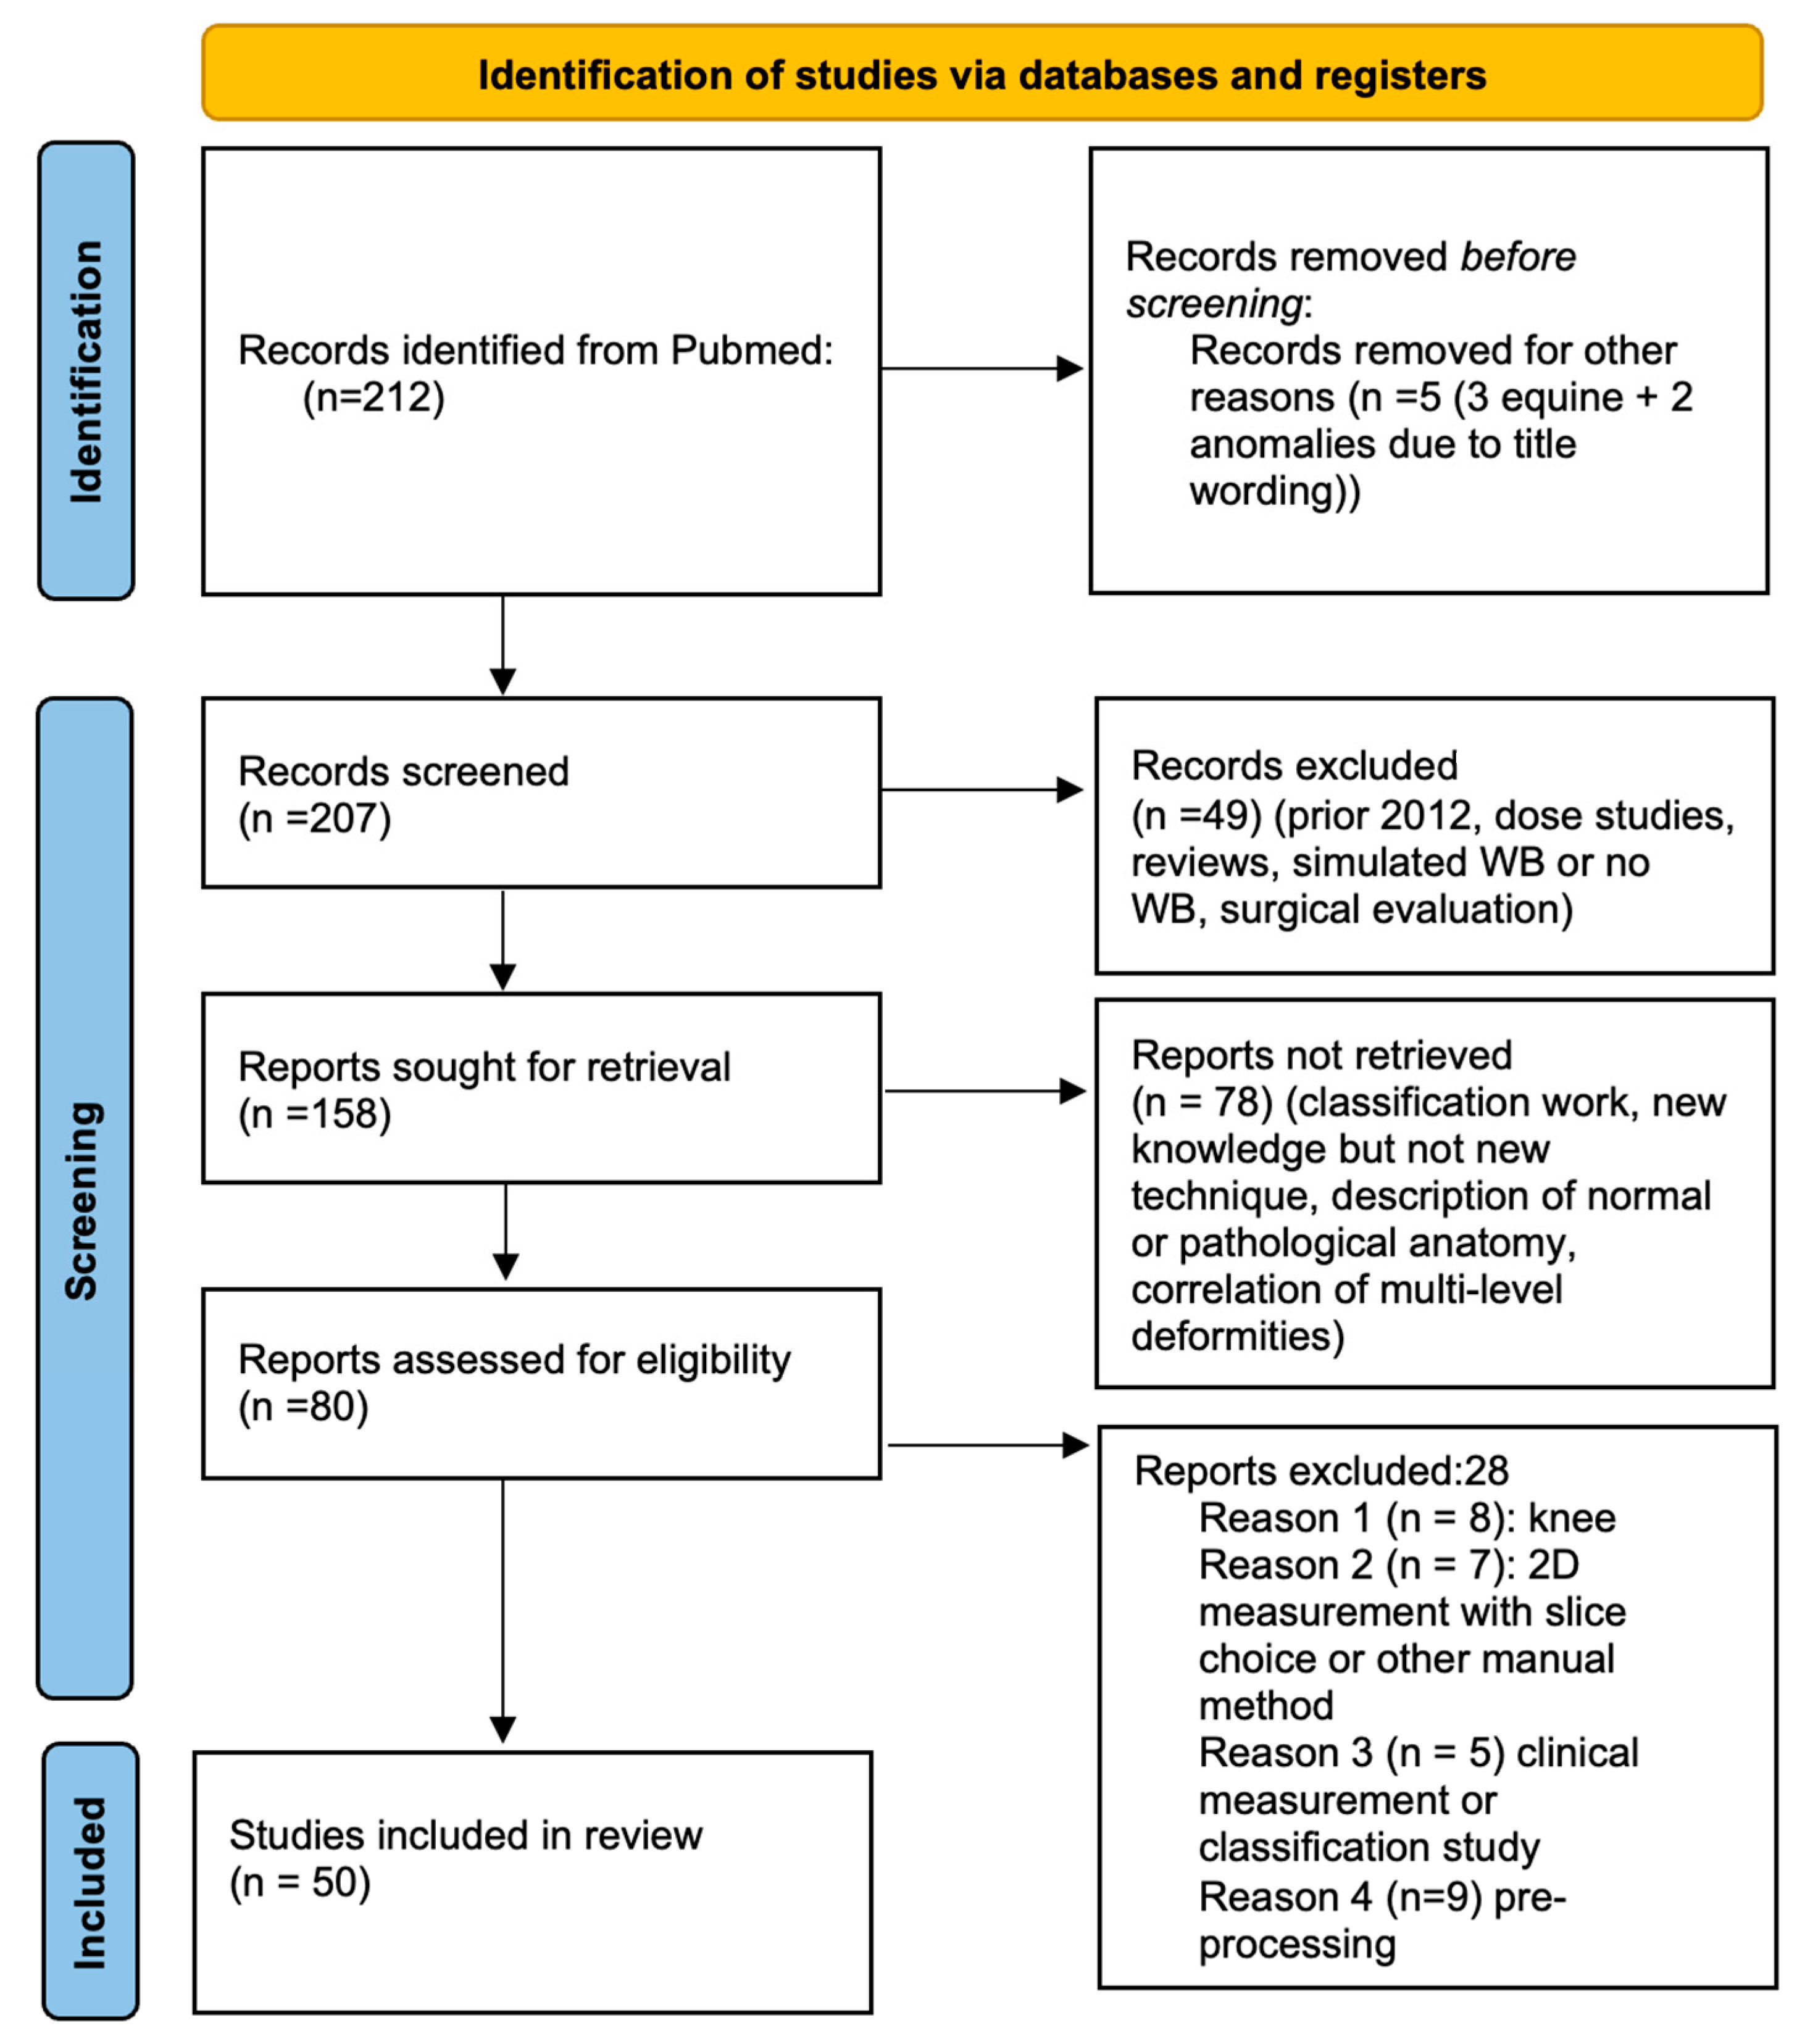

2. Materials and Methods

3. Results

3.1. Pre-Screening

3.2. Screening

- Studies prior to 2012

- Studies of radiation dosage

- Simulated weight-bearing or absence thereof

- Use of WBCT for evaluation of surgical results without innovative methods

- WBCT classifications

- New knowledge but absence of an innovative technique

- Description of normal or pathological anatomy

- Multi-level biomechanical investigation

- Innovative WBCT techniques; study concerning the knee (8 studies)

- Two-dimensional method performed within 3D volume (7 studies)

- Clinical measurement or classification study (5 studies)

- Pre-processing techniques (9 studies)